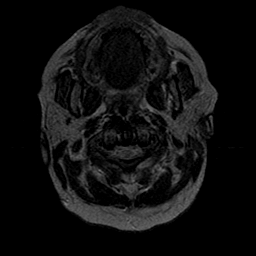

Cerebral hemorrhage, MR Study mr-t2 -- Slice #0

[Home][Help][Clinical] Slice 0